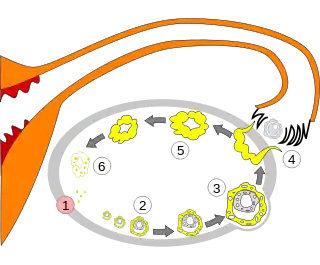

Order of changes in ovary